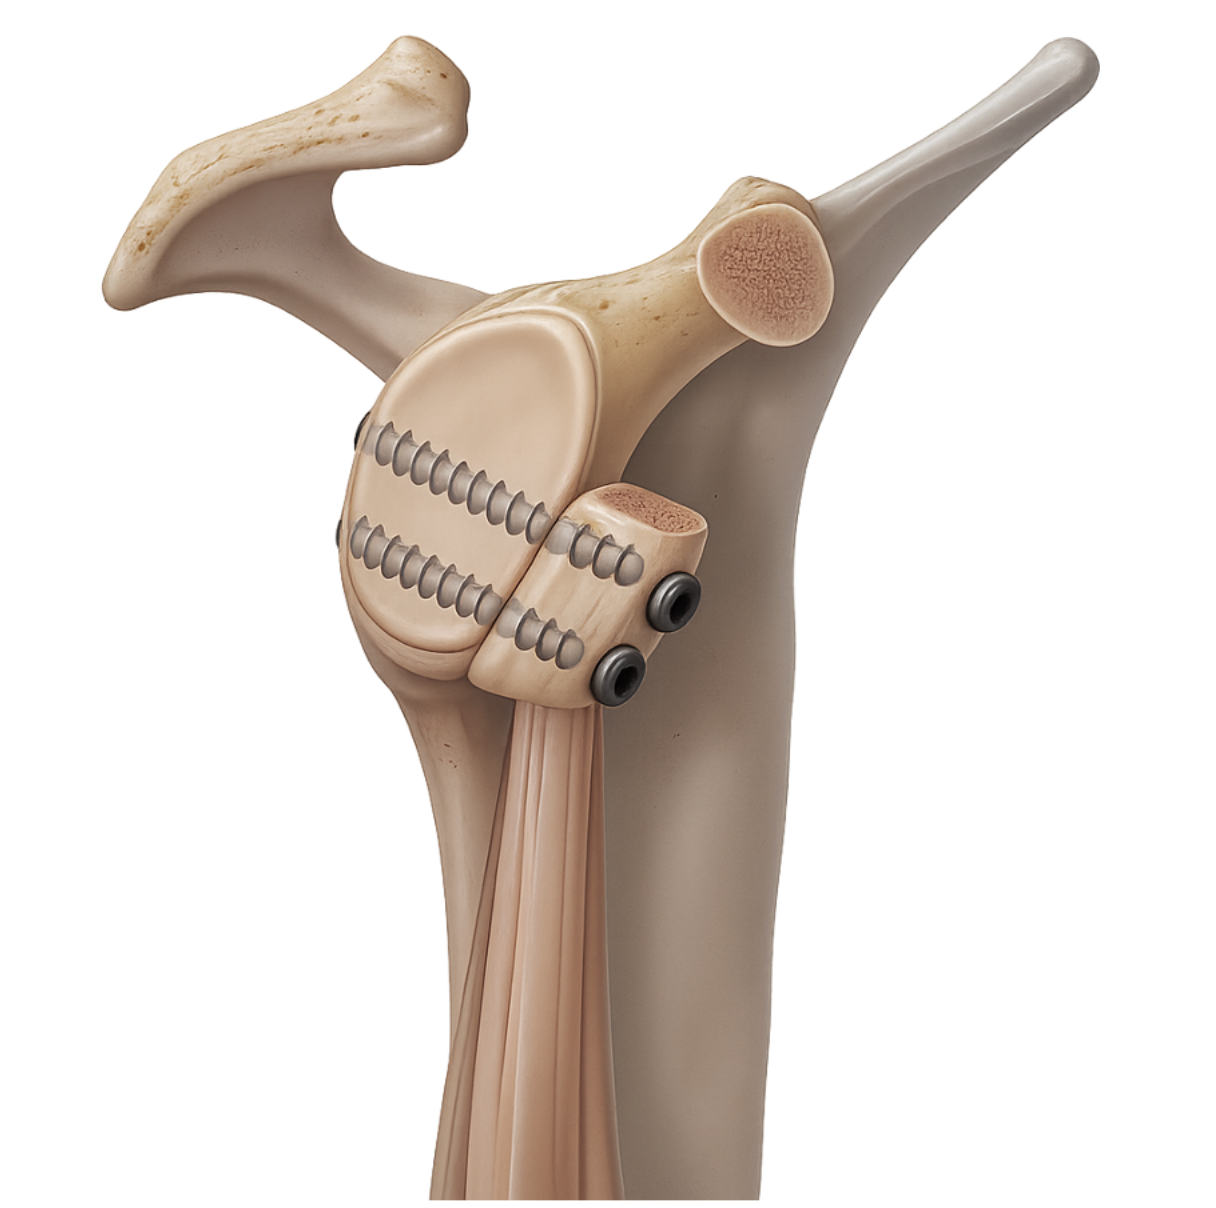

Le principe est de prélever un petit fragment d’os appelé processus coracoïde (sur lequel s’insère notamment une partie du tendon du biceps), puis de le fixer sur le bord antérieur de la glène.

Cette butée osseuse empêche la tête humérale de passer en avant de la glène lors des mouvements à risque. Elle est fixée par une ou deux vis.

Le tendon du biceps (tendon conjoint) et la tension du muscle sous-scapulaire (traversé pour mettre en place la butée) contribuent également à empêcher une nouvelle luxation.